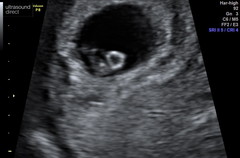

I had my first early scan today too at 8+5. Looked like a tiny teddy bear with little arma and legs and was wriggling around 😂 measured exactly 8+5 and had a strong heart beat. There was also another sac with visible kill sac 🙈 But doc reckoned that the second one likely wasn't viable and might get reabsorbed, I have to go back for a second scan in 2 weeks to check. It kind of make sense to me I think because I was incredibly nauseous on week 6 and then it faded way back, although didn't disappear completely. I am just looking at the positives that there is one viable baby in there, and remembering that if I hadn't had an early scan I likely wouldn't have even known about the second one.